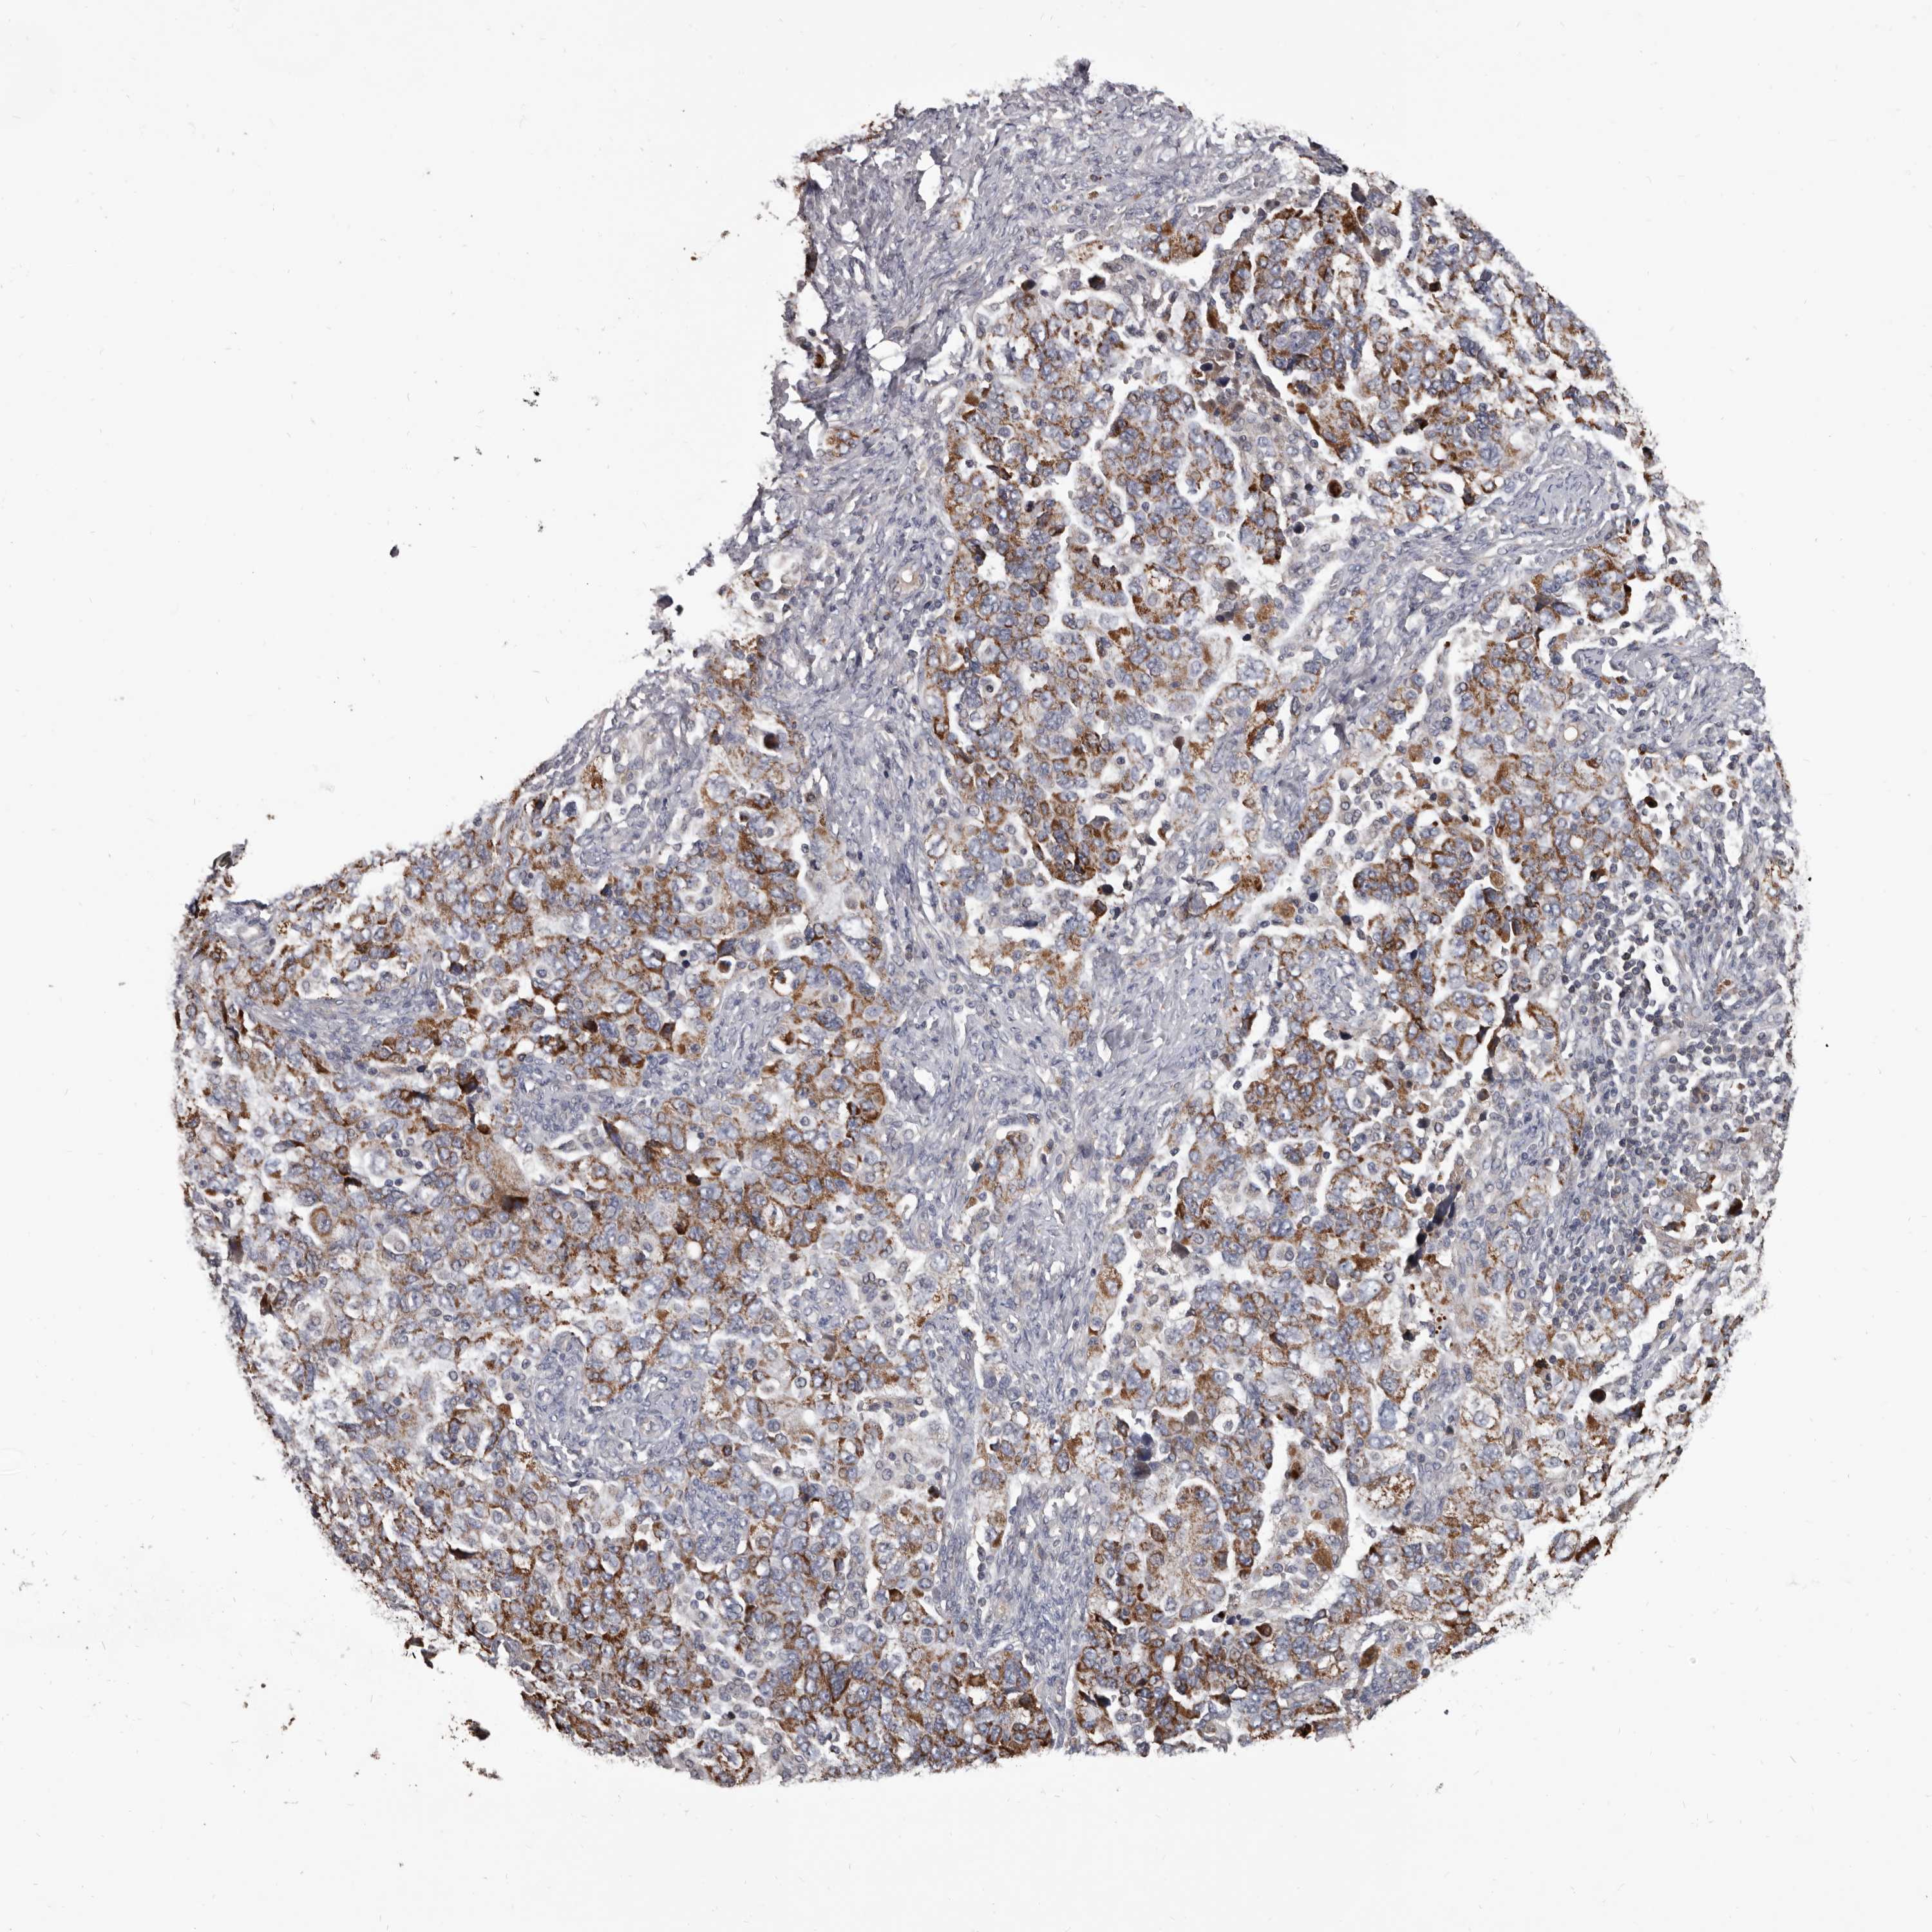

OVARIAN CANCER - Protein expressioni

A mouse-over function shows sample information and annotation data. Click on an image to view it in a full screen mode. Samples can be filtered based on level of antibody staining by selecting one or several of the following categories: high, medium, low and not detected. The assay and annotation is described here.

Note that samples used for immunohistochemistry by the Human Protein Atlas do not correspond to samples in the TCGA dataset.

Antibody stainingi

Antibody staining in the annotated cell types in the current human tissue is reported as not detected, low, medium, or high, based on conventional immunohistochemistry profiling in selected tissues. This score is based on the combination of the staining intensity and fraction of stained cells.

Each image is clickable and will lead to virtual microscopy that enables deeper exploration of all samples and also displays staining intensity scores, fraction scores and subcellular localization as well as patient and tissue information for each sample.

Antibody HPA029715

Antibody HPA029716

Cystadenocarcinoma, serous, NOS